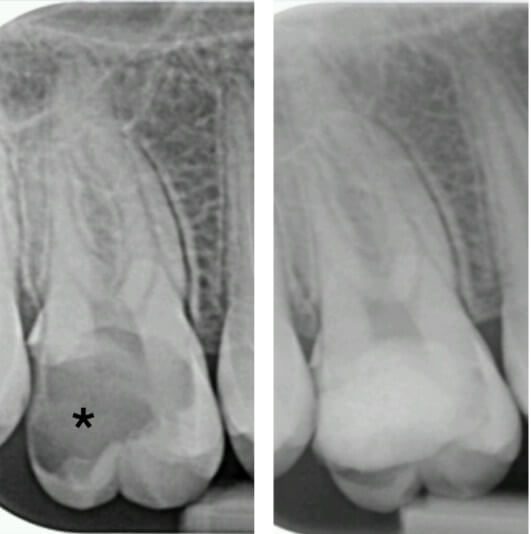

Initially, patients may only experience some warning signs, but the more the infection penetrates into deeper dental layers and towards the pulp (Fig. 2), the more the body’s inflammatory response intensifies, transforming minor discomfort into significant pain. At this stage, called pulpitis, traditional treatments shift from conservative restoration to more invasive procedures like pulp excision and endodontic therapy [25].

Fig. 2.

Intraoral X-ray of tooth #16 before and after carie (*) treatment.